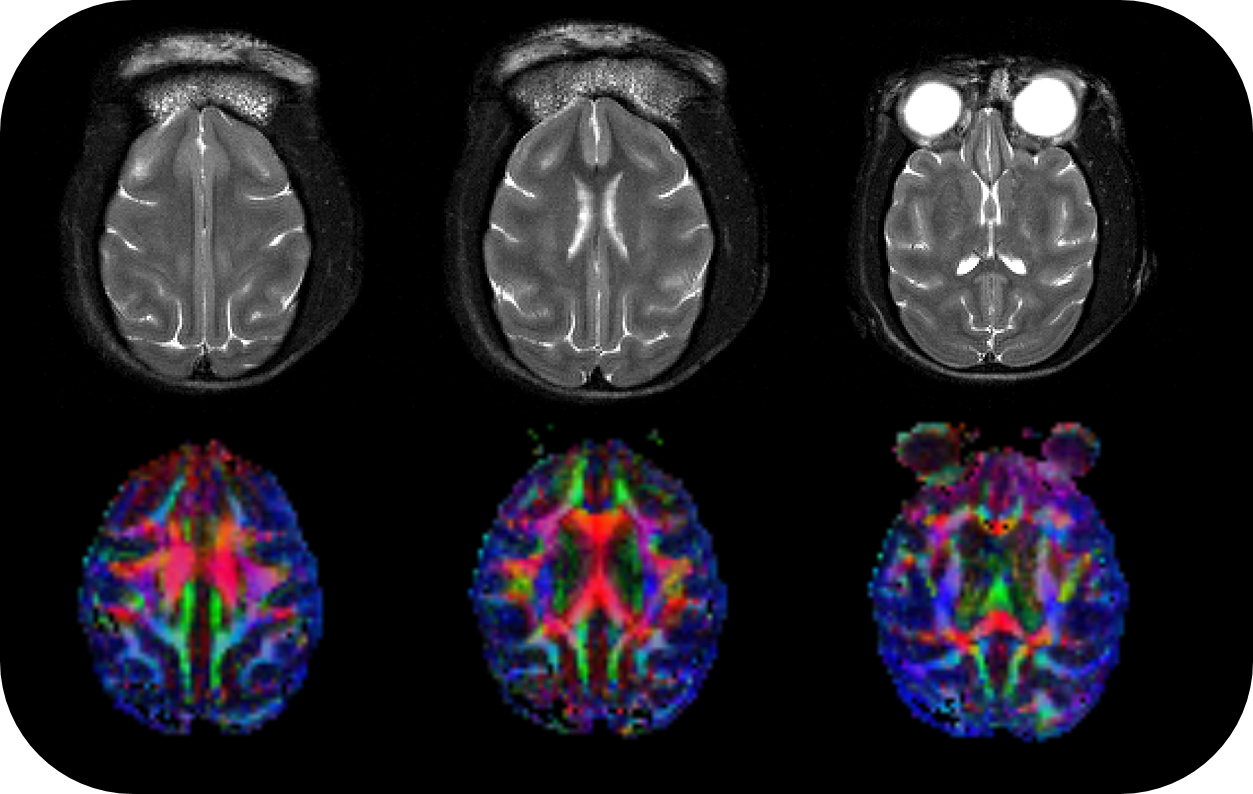

BioSpec 70/30 and 94/30

Studies with intricate set-ups or on animals up to the size of rabbits can be conducted with the extremely physically stable, 30 cm bore size BioSpec 70/30 and BioSpec 94/30.

ParaVision

ParaVision® 360:

• Intuitive software package, for multi-dimensional MRI/MRS data acquisition, visualization, reconstruction, and analysis of MRI and/or PET/MR data

• MRI sequence portfolio of more than 1,000 sequence variations, including wireless cardiac imaging using navigator based IntraGate methods with cartesian or radial readout, as well as short echo time imaging, such as UTE and ZTE